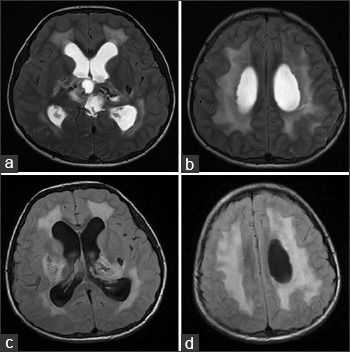

На МРТ головного мозга определялись обширные области гиперинтенсивного в Т2ВИ и FLAIR сигнала, которые затрагивали перивентрикулярные области белого вещества, оставляя интактными U-волокна и мозолистое тело с кистозными включениями и признаками обструктивной гидроцефалии. Обнаруженные ранее на КТ кальцинаты были гипоинтенсивны в Т2- и Т1ВИ и показывали «выпадение» МР-сигнала в GRE.

На аксиальных Т2ВИ (a, b) и FLAIR (с, d) томограммах можно увидеть обширные области гиперинтенсивности белого вещества мозга, что говорит о лейкоэнцефалопатии.

Аксиальные Т1 и Т2ВИ сканы демонстрируют кисты в обеих гемисферах мозжечка, расположенные над третьим желудочком в пинеальной области; обратите внимание на расширение боковых желудочков в результате обструктивной гидроцефалии.

Области “выпадения” МР-сигнала на GRE в области базальных ядер, таламусов и ядер мозжечка соответствуют кальцинатам.